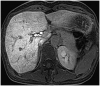

During chemotherapy in patients with gastrointestinal malignancy, the hepatic lesions may occur as chemotherapy-induced lesions or tumor-associated lesions, with exceptions for infectious conditions and other incidentalomas. Focal hepatic lesions arising from chemotherapy-induced hepatopathies (such as chemotherapy-induced sinusoidal injury and steatosis) and tumor-associated eosinophilic abscess should be considered a mimicker of metastasis in patients with gastrointestinal malignancy. Accumulating evidence suggests that chemotherapy for gastrointestinal malignancy in the liver has roles in both the therapeutic effects for hepatic metastasis and injury to the non-tumor bearing hepatic parenchyma. In this article, we reviewed the updated concept of chemotherapy-induced hepatopathies and tumor-associated eosinophilic abscess in the liver, focusing on the pathological and radiological findings. Awareness of the causative chemo-agent, pathophysiology, and characteristic imaging findings of these mimickers is critical for accurate diagnosis and avoidance of unnecessary exposure of the patient to invasive tissue-based diagnosis and operations.